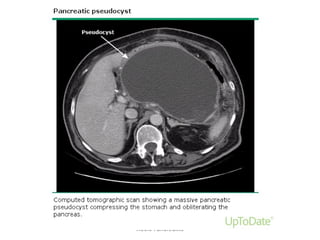

PseudocystsPseudocysts

• Collection of pancreatic fluid enclosed by non-

epithelialized wall of granulation tissue

• Complicates 5-10% cases of AP

• ~ 4 weeks after insult

• 25-50% resolve spontaneously